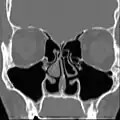

Bij onderzoek zou de neusholte er abnormaal ruim uit moeten zien door het ontbreken van (een deel van) de onderste en/of middelste neusschelpen. Slijmvliespathologie varieert sterk. Bij sommige patiënten is het slijmvlies droog en bleek als gevolg van metaplasie, in andere is het rood als gevolg van chronische ontsteking. Korstvorming kan variëren van afwezig tot ernstig. De symptomen en bevindingen worden verondersteld te worden veroorzaakt door abnormale aerodynamica, chronische ontstekingen en droogte, die leiden tot het verlies van het voelen van luchtstroom, hetgeen voelt als benauwdheid.[17]

Empty Nose Syndrome na subtotale onderste conchotomie.

Alle neusschelpen verwijderd – Aanblik van rechter laterale wand.

Anatomie van de neusholte